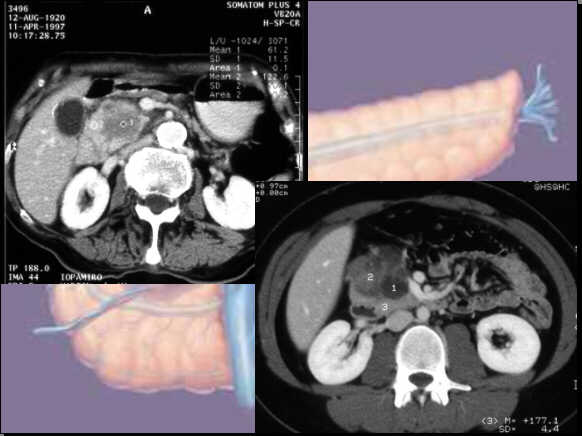

Generally the differentiation is problematic:

Enlarged

pancreatic head with hypodense lesion. Indistinct

border between the pancreas and the retroperitoneal space: Ductal

adenocarcinoma.

pancreatic head with hypodense and cystic lesions.

Involvement of mesenteric artery: Ductal adenocarcinoma.